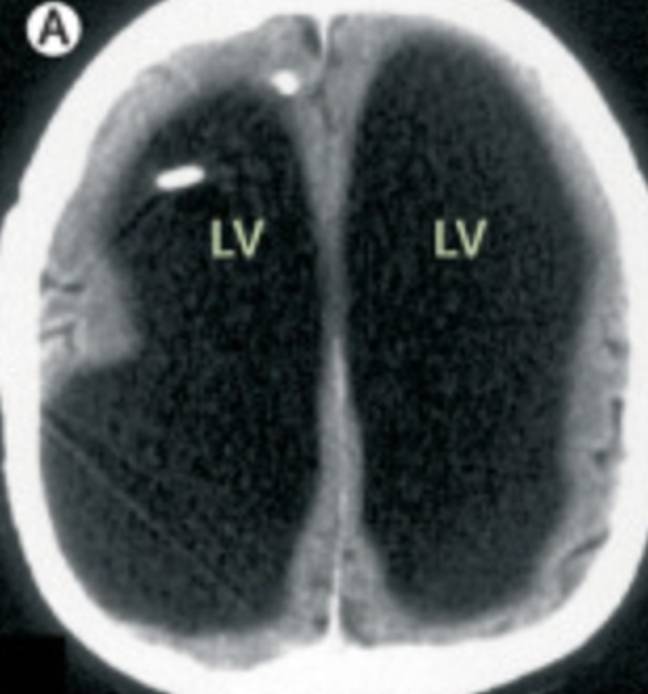

Magnetic Resonance Imaging Brain Showing Loss Of Flow Void With High

FLAIR And T2W Images Of Brain Demonstrate Loss Of Flow Void In Right